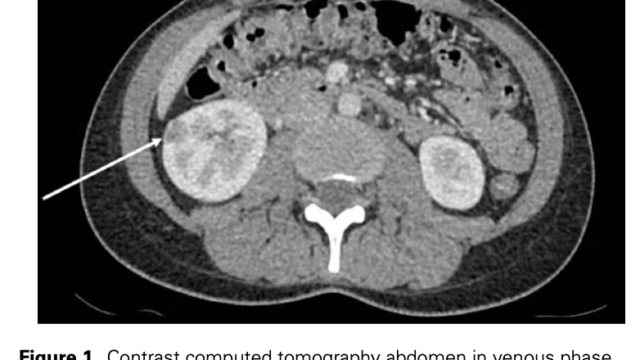

IgMPC-TINとPBC、SjSでは下図のような関係が示されている。